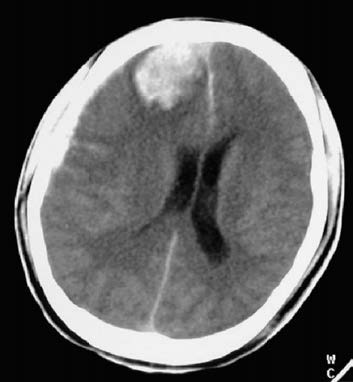

The symptoms of intracerebral hematoma are very similar to those of subdural hematoma accompanied by cerebral contusions and lacerations. CT imaging shows round or irregular hyperdense lesions near the site of brain contusions or within the deep white matter.

Figure 1 Intracerebral hematoma (CT, right frontal lobe)